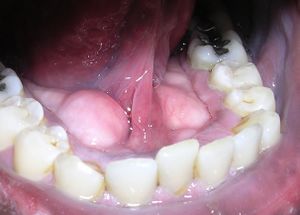

اللّويحة السّنّيّة Dental plaque عبارة عن بيوفيلم متراكم على الأسنان، تتميّز بلونها الأصفر الشاحب.

اكتشاف اللويحات عادة ما يتم سريرياً بكواشف اظهار اللويحات. وتحتوي كواشف اظهار اللويحات صبغة تتحول إلى اللون الأحمر الزاهي لبيان تراكم اللويحات.